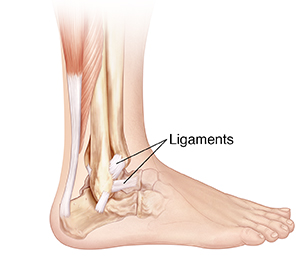

Understanding Ankle Sprain

The ankle is the joint where the leg and foot meet. Bones are held in place by connective tissue called ligaments. When ankle ligaments are stretched to the point of pain and injury, it's called an ankle sprain. A sprain can tear the ligaments. These tears can be very small but still cause pain. Ankle sprains are graded by the amount of ligament damage.